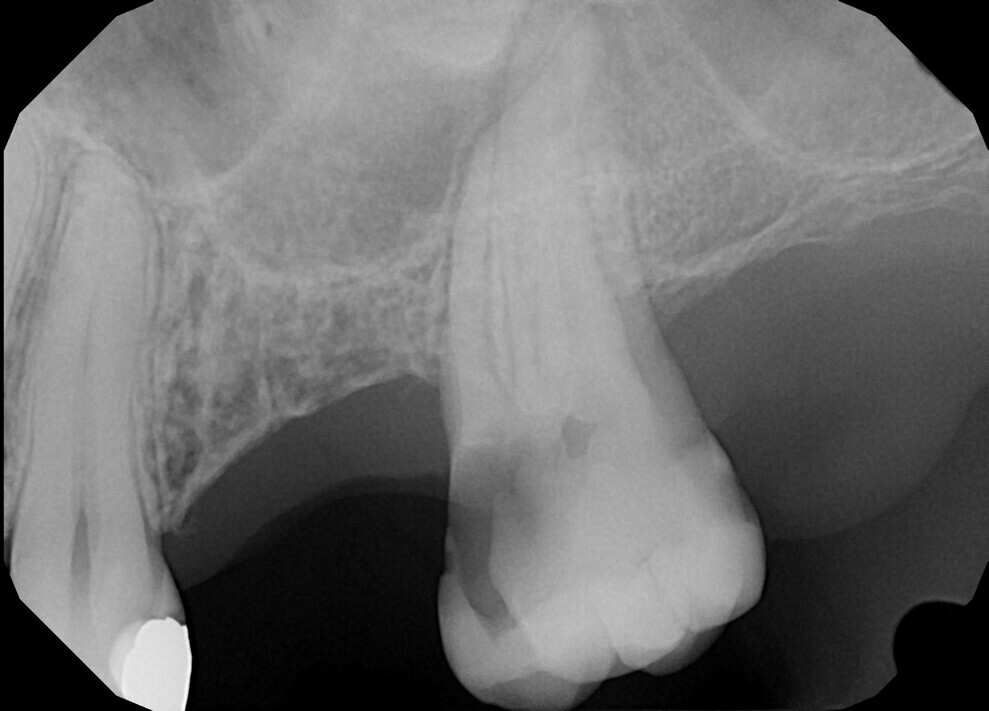

Case 1

A 43-year-old patient came to our office having been referred for endodontic treatment. During oral examination, a deep carious lesion in tooth #27 was visible. Radiographic examination confirmed the diagnosis (Fig. 6). After gingivectomy with a gingiva trimmer bur (JOTA), which was necessary in order to create space for proper isolation (Figs. 7–9), the cavity was cleaned and prepared for build-up.